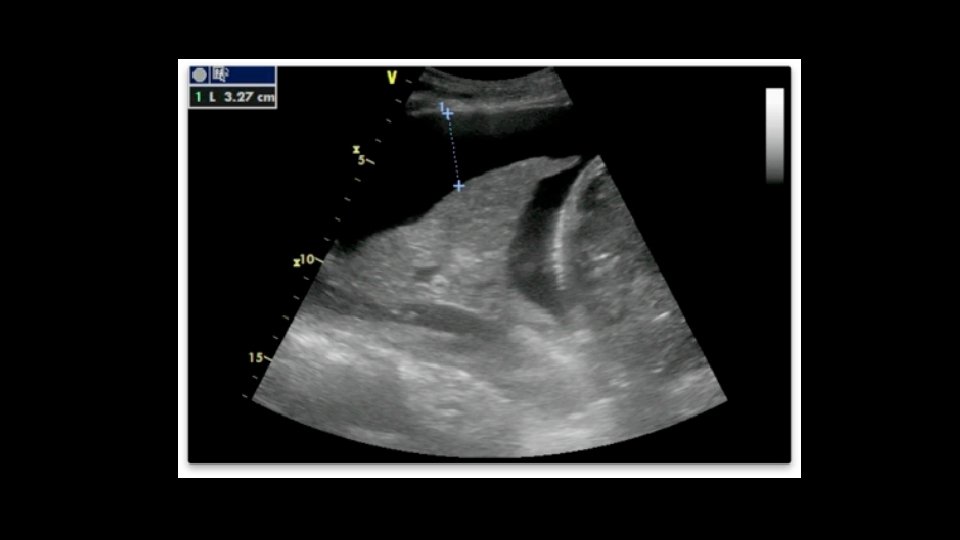

Perisplenic Recess • Posterior axillary line • 5 -7 th intercostal space • “knuckles to the bed”

Perisplenic